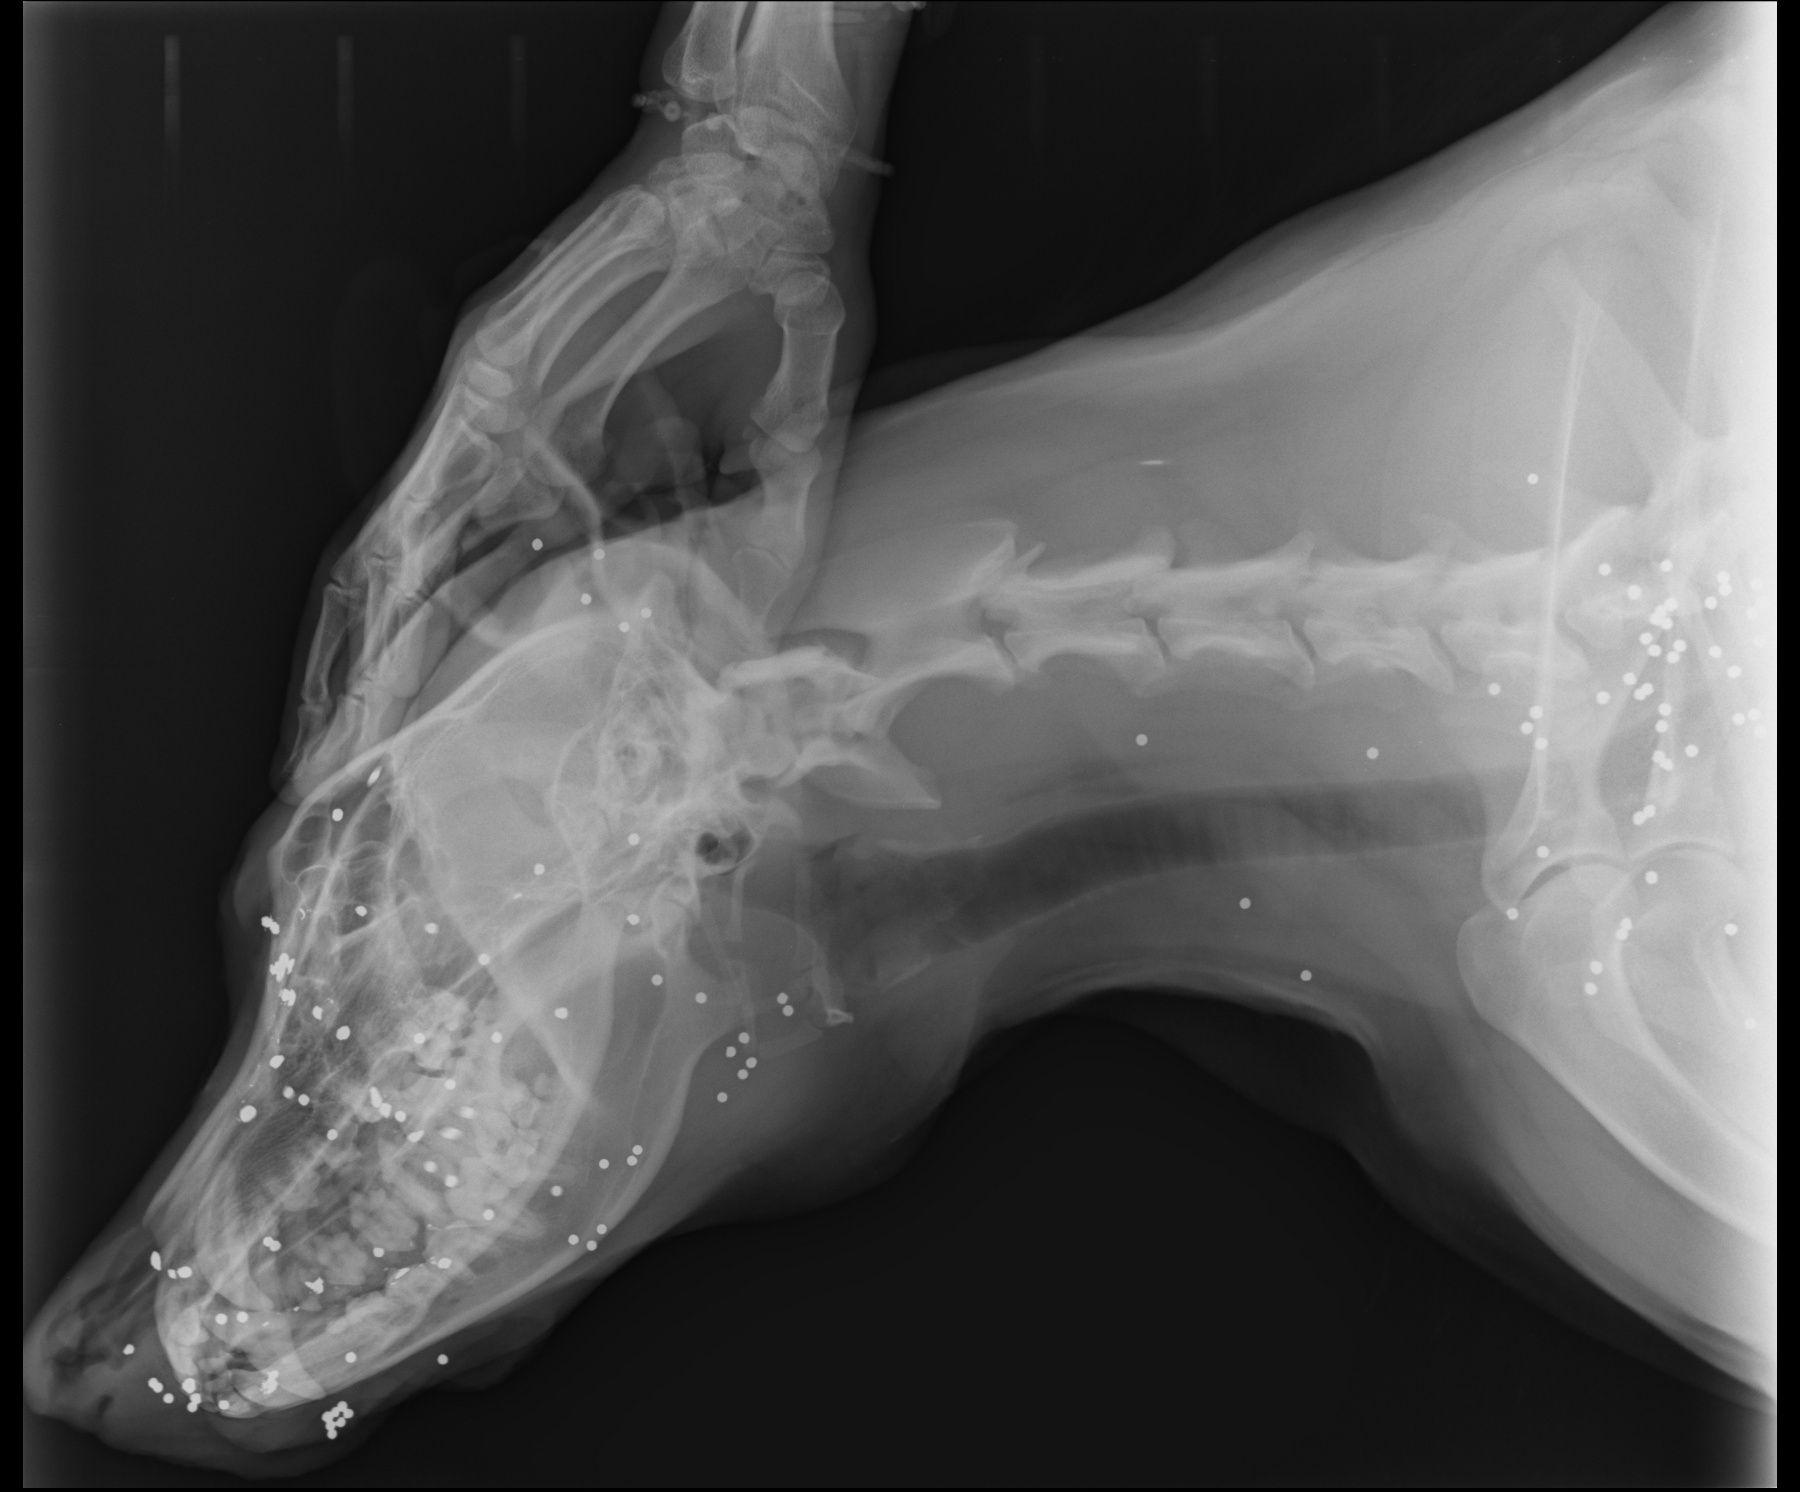

O τραυματισμένος σκύλος που μεταφέρθηκε για νοσηλεία στο κτηνιατρείο του Στάθη Πιτταρά έχει στο κεφάλι, στον τράχηλο και στο αριστερό του πόδι περισσότερα από 160 σκάγια.